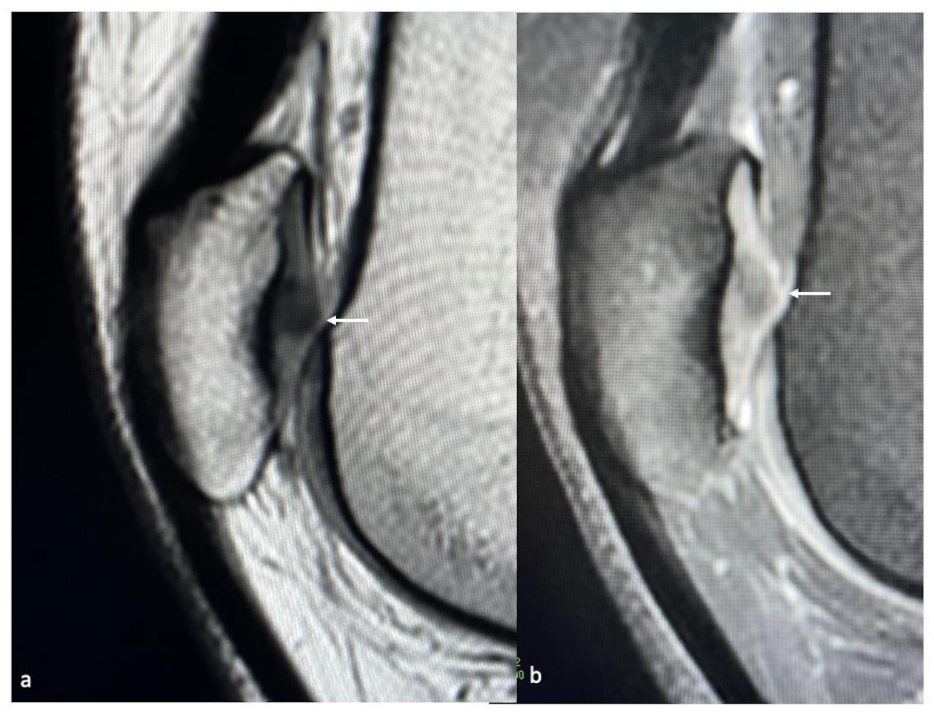

3.4. MRI

| Berndt and Harty (X-ray) | Loomer et al. [57] Modification (CT) | Hepple et al. [58] (MRI) |